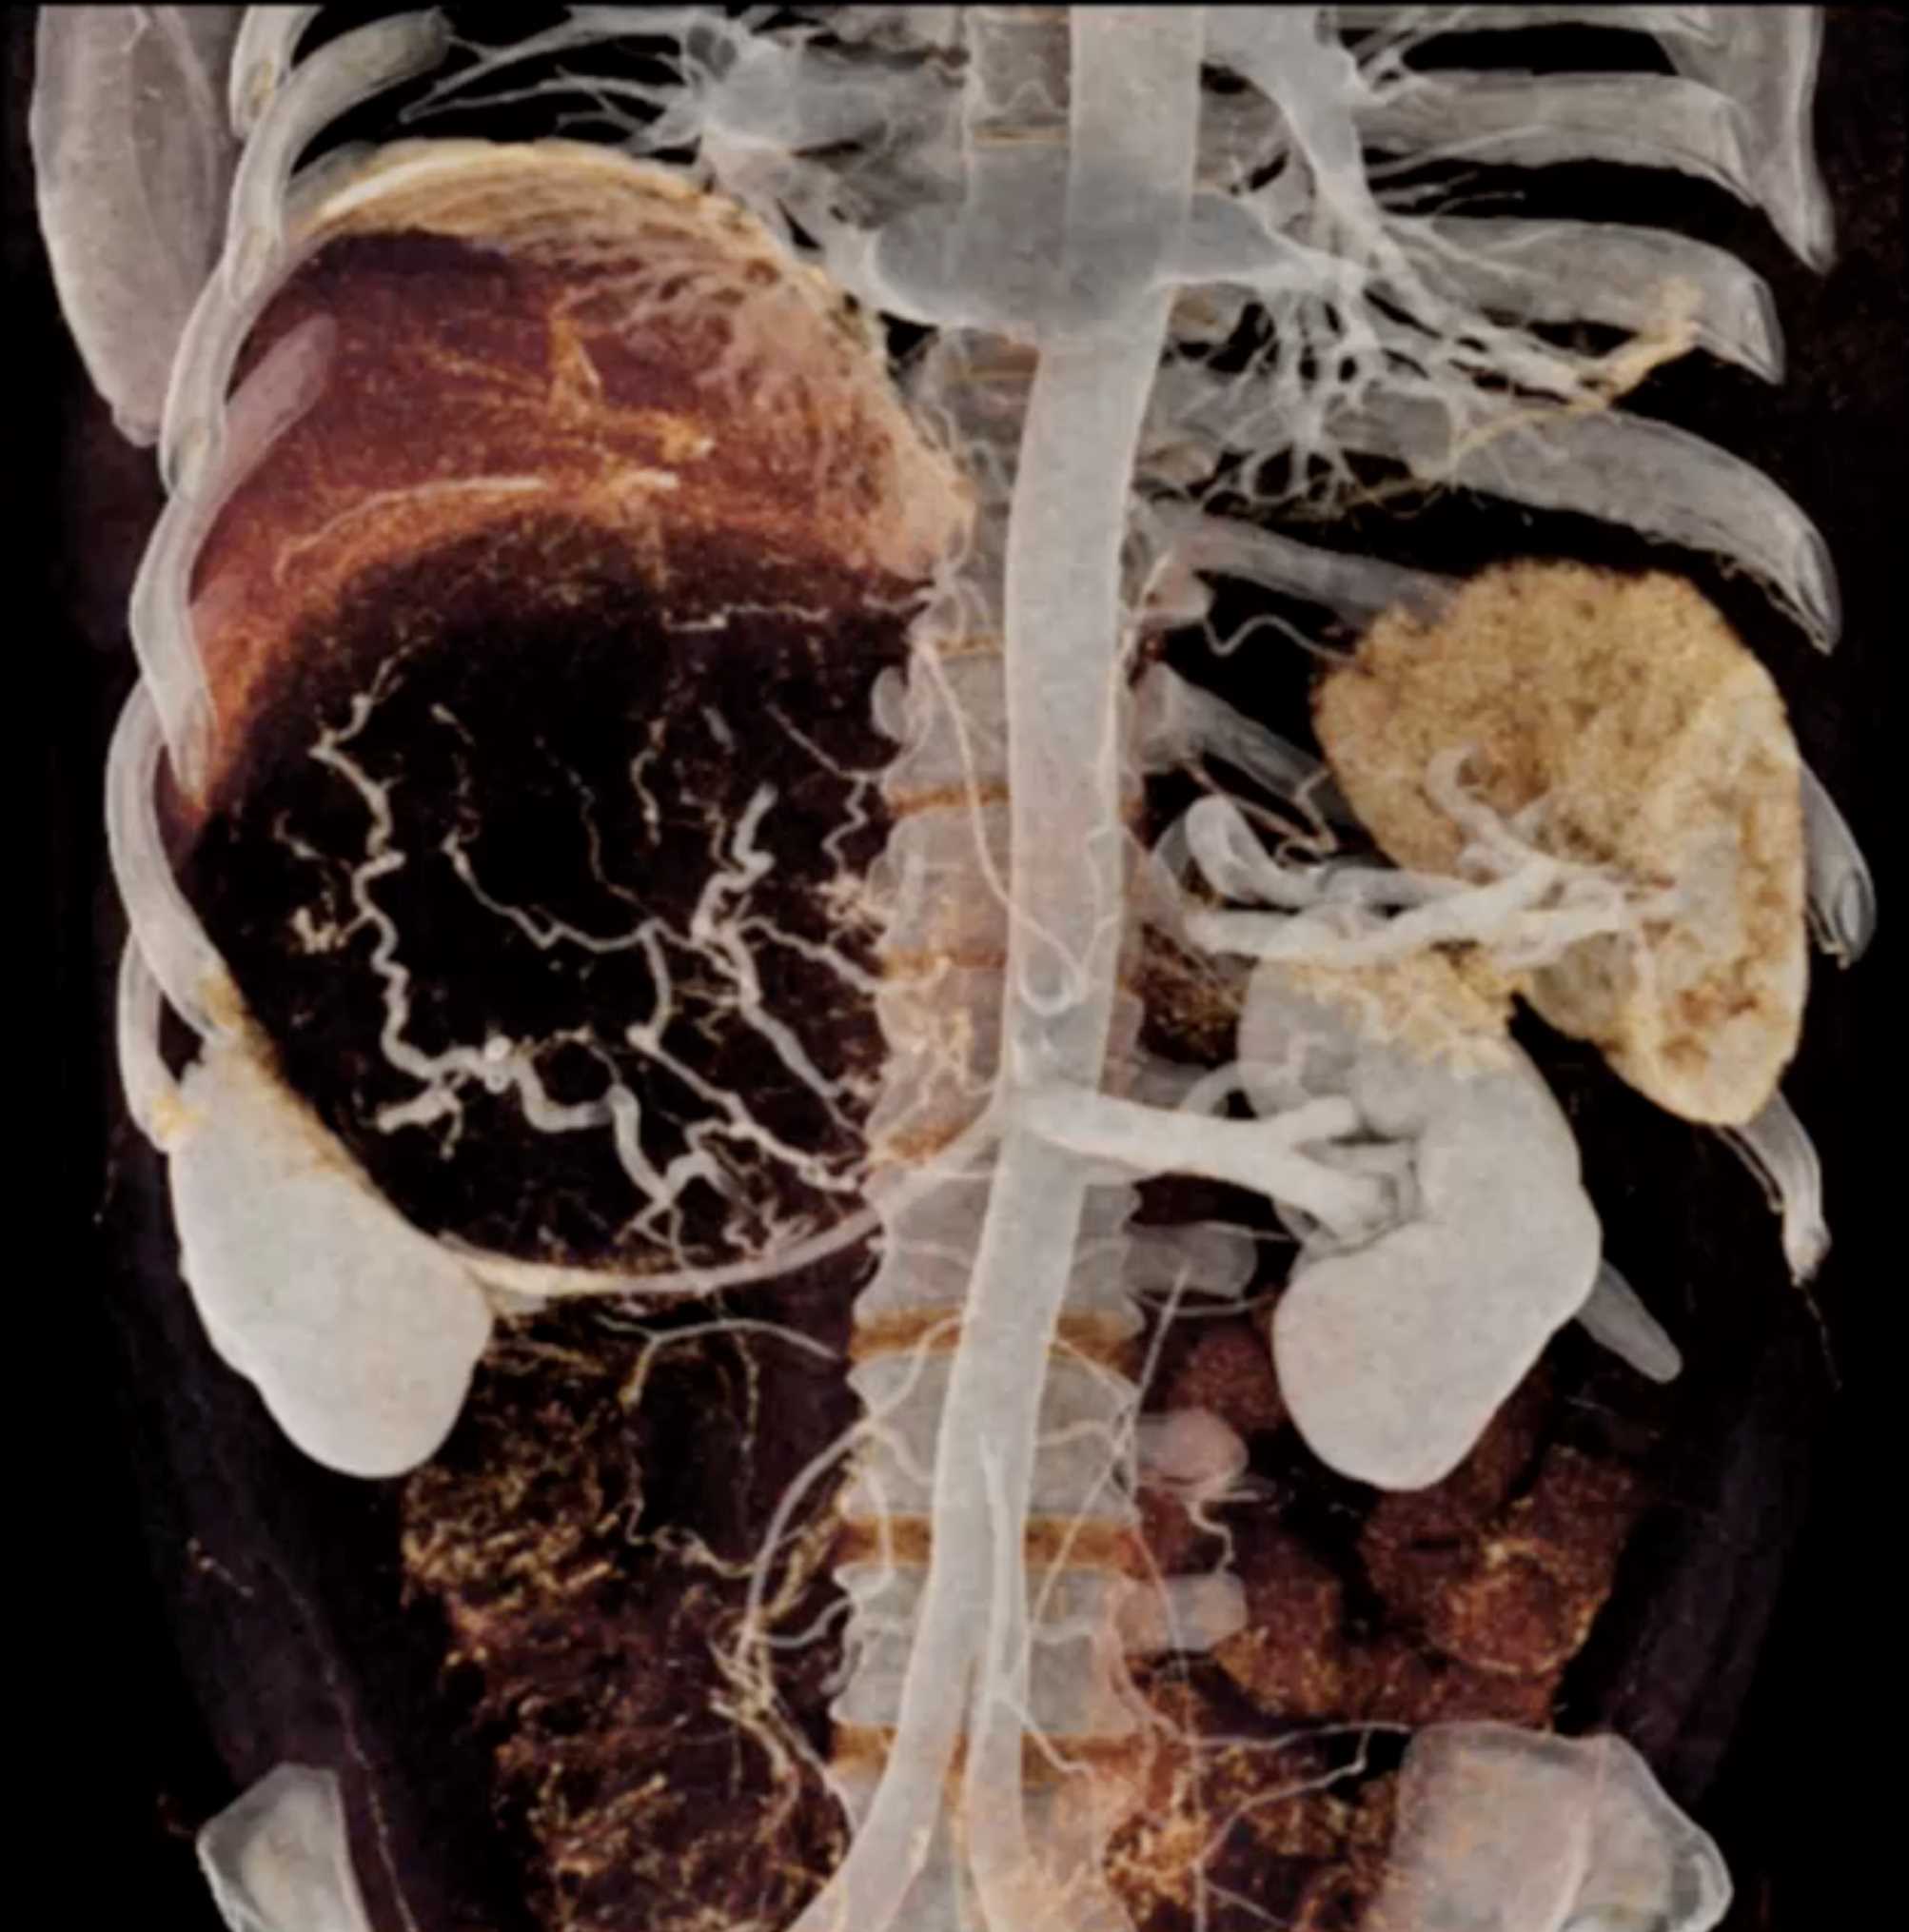

Left Adrenal Metastases from Renal Cell Carcinoma